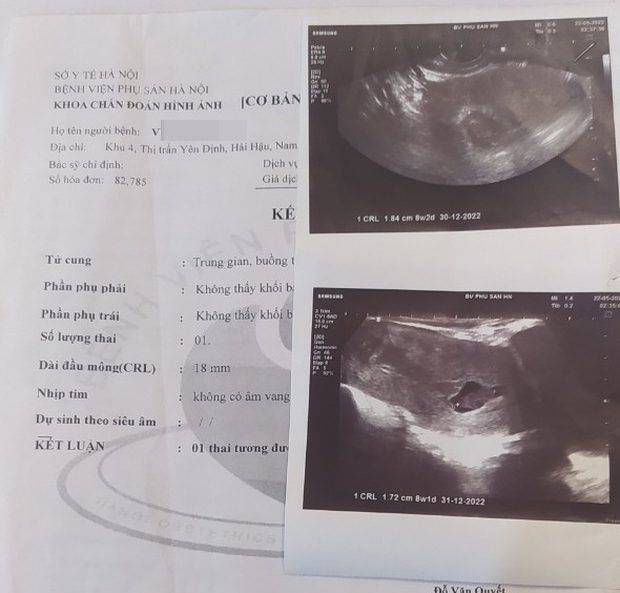

Kết quả siêu âm của Bệnh viện Phụ sản Trung ương

Hình ảnh siêu âm tim thai

Theo kết quả, siêu âm của bệnh nhân V.T.Tr. bác sĩ kết luận: "1 thai tương đương 8 tuần 2 ngày, theo siêu âm, ngừng phát triển".